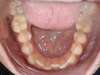

Cas 3 : Description

Encombrement aux deux arcades.Traitement par gouttières.

Avant

Après